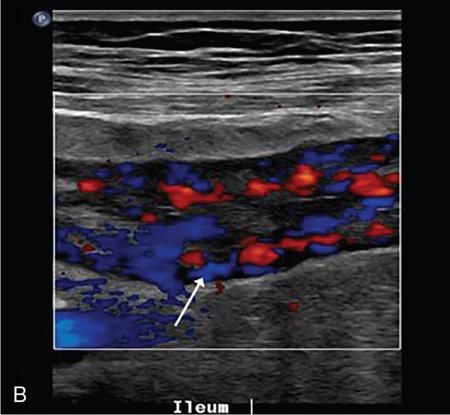

Kavita Saggar, Archana Ahluwalia, Devinder Pal Singh Dhanota, Geetika Khanna, Chander Gupta Inflammatory bowel disease (IBD) represents chronic idiopathic inflammation of the gastrointestinal [GI] tract. The common subtypes are Crohn’s disease, ulcerative colitis (UC) and indeterminate colitis (Fig. 7.11.1). Approximately 20%–25% of patients present in childhood or adolescence. Of these, nearly two-thirds of cases are caused by Crohn’s disease with an incidence of 4.56 per 1000,000 children (Fig. 7.11.2). IBD can affect any portion of the GI tract; however, children have a much higher incidence of small bowel and colonic involvement (Table 7.11.1). Currently, there is no single diagnostic test for the evaluation of IBD. Diagnosis is based on a combination of history, physical examination, serum inflammatory markers, endoscopy, histopathology and imaging. A host of imaging modalities is available for the evaluation of IBD in children. Traditionally, barium fluoroscopic studies, namely small bowel follow-through or small bowel enteroclysis (SBE) were used. However, barium studies depict only the mucosal abnormalities and do not evaluate the extraluminal extent of disease. Ultrasonography (US) is increasingly being used in the workup of patients with IBD. Small intestine contrast ultrasound (SICUS) and contrast-enhanced ultrasound (CEUS) are used for evaluation of IBD. CEUS requires intravenous administration of microbubble contrast such as Sonovue, and SICUS requires small bowel adequate luminal distension with ingestion of an iso-osmolar contrast agent such as polyethylene glycol. A recent meta-analysis of 33 studies showed that CEUS had better accuracy than US, CT and MR for the detection of inflammation and differentiation of fibrotic and inflammatory strictures. However, the extent of the disease was better evaluated by CT and MR. Currently, computed tomography enterography (CTE) and magnetic resonance enterography (MRE) have emerged as the most effective tools for imaging small bowel in patients with IBD. CTE and MRE can accurately depict the spectrum of imaging findings related to severity, extent and complications of IBD and thereby help in guiding management and assess the response to treatment. MRE is an attractive imaging modality due to lack of ionizing radiation, inherent multiplanar capability and excellent soft tissue contrast resolution. In addition, dynamic/cine imaging allows assessment of peristalsis and accurate identification of the diseased segment. The major disadvantage of MRE is high cost, lower spatial and temporal resolution and long examination time. Crohn’s disease is a transmural granulomatous disease that can affect any part of the GI tract from the oral cavity to anus, often involving multiple discontinuous segments of bowel. Patients have a genetic predilection to develop an abnormal immunologic response to environmental factors including food and gut flora, leading to a chronic inflammatory response. Small bowel is the major site of involvement. Terminal ileum is the most common location which is involved in approximately one-third patients. The colon is affected in 50% patients. In 15%–20% cases, there may be isolated involvement of the colon without affecting the small bowel. The clinical importance of small bowel Crohn’s disease is the impact that a diffuse small bowel disease is expected to have on child’s growth and development. Thus, objective evaluation of small bowel is essential in differentiating from other enteropathies and in directing the management of patients with IBD. Two methods used for imaging small bowel with barium using fluoroscopy are standard small bowel follow through (SBFT) and SBE. Small bowel evaluation with barium has long been considered the most common, noninvasive, inexpensive and easily accessible radiological method, but it has been replaced by cross-sectional imaging. In the current scenario, the only indication of barium studies is when CTE or MRE cannot be done because of nonavailability or are not feasible. Ultrasound is being increasingly used to assess the activity of Crohn’s disease, especially in paediatric patients. Greyscale ultrasound allows morphologic assessment of bowel wall and mesentery. Normal small bowel loops are easily compressible with the transducer and the wall thickness is <2 mm. The bowel loops show regular peristalsis and are mobile. Colour Doppler shows minimal intramural or perienteric vascularity. The salient sonographic features of Crohn’s disease are: There is marked concentric or eccentric bowel wall thickening [>2.5–3 mm]. The mural echogenicity depends upon the degree of inflammation and fibrosis. In the acute phase, mural stratification is maintained (Fig. 7.11.3A and B). In patients with long-standing disease, a target or pseudo-kidney appearance may be seen. In long-standing burnt-out disease, there is submucosal fat deposition. The actively inflamed bowel segments show increased vascularity on Doppler ultrasound (Fig. 7.11.4A and B). CEUS with microbubbles can objectively assess the disease activity. A stricture is seen as a segment of bowel wall thickening with apposition of the luminal surfaces. There is persistent luminal narrowing with variable degree of upstream dilatation and hyperperistalsis. Doppler imaging reveals hyperemia in strictures with an active inflammatory component. Fibrotic strictures do not demonstrate increased blood flow. A major advantage of ultrasound is real-time imaging which allows the evaluation of bowel peristalsis. The diseased segments of the bowel (inflamed or fibrotic) show reduced peristalsis and often appear fixed in position. Mesenteric inflammation is commonly seen in active Crohn’s disease. Sonography reveals thickening of mesentery with heterogeneous echogenicity due to oedema. Doppler ultrasound shows increased vascularity due to engorgement of vasa recta. Fibrofatty proliferation of mesentery seen in chronic disease appears as abnormally thickened echogenic fat that displaces the bowel loops. Reactive mesenteric lymph nodes (up to 1.5 cm) can be seen in the active inflammatory phase of Crohn’s disease. These appear as hypoechoic round or oval structures with preserved fatty hilum. Sinus tracts and fistula often arise from or just proximal to a strictured segment and appear as linear areas of altered hypoechogenicity extending from serosal surface of gut. There may be tethering and/or angulation of the affected bowel segment. Abscesses are discrete well-defined fluid collections with internal debris, septation or nondependent echogenic gas. Colour Doppler reveals peripheral hyperemia with absent blood flow centrally. Ultrasound may be falsely negative if an abscess contains a large amount of air and can be mistaken for an air-filled bowel loop. Both CTE and MRE identify the transmural, extramural and mesenteric manifestations of small bowel Crohn’s disease. The imaging findings can be categorized as: Asymmetric long segment (>3 cm) bowel wall thickening is a consistent feature of Crohn’s disease. The mesenteric border is usually more severely affected. It is imperative that the bowel should be distended when assessing bowel wall thickening. Thickening may be mild (3–4 mm), moderate (5–10 mm) or severe (>10 mm) (Fig. 7.11.5A and B). This is the most consistent finding in the active inflammatory stage, defined as increased signal intensity or attenuation on contrast-enhanced scans in a noncontracted segment of bowel in comparison with adjacent small bowel segments. Hyperenhancement may be stratified into bilaminar and trilaminar patterns. In the bilaminar pattern, there is hyperenhancement of only the inner wall (often referred to as mucosal hyperenhancement), and in the trilaminar pattern, there is inner and outer wall hyperenhancement, with the submucosal oedema giving a halo effect. Hyperenhancement may also be homogeneously transmural or patchy. A potential pitfall in contrast enhancement is that normal jejunal loops enhance more than ileal loops and collapsed bowel segments can show apparent hyperenhancement (Figs. 7.11.6A,B and 7.11.7A–C). These are defined as multifocal (>3) segmental areas of involvement with normal intervening gut loops. This is an important feature that differentiates Crohn’s disease from UC when colon is predominantly involved (Figs. 7.11.5A,B and 7.11.7A–C). This is identified as an increased signal of the thickened bowel wall on T2W images. The inflamed walls also show restricted diffusion. The hyperintense signal due to intramural oedema persists on T2W fat-saturated images differentiating it from intramural fat seen in long-standing burnt-out disease (Fig. 7.11.8A and B; refer Fig. 7.11.20A–D).